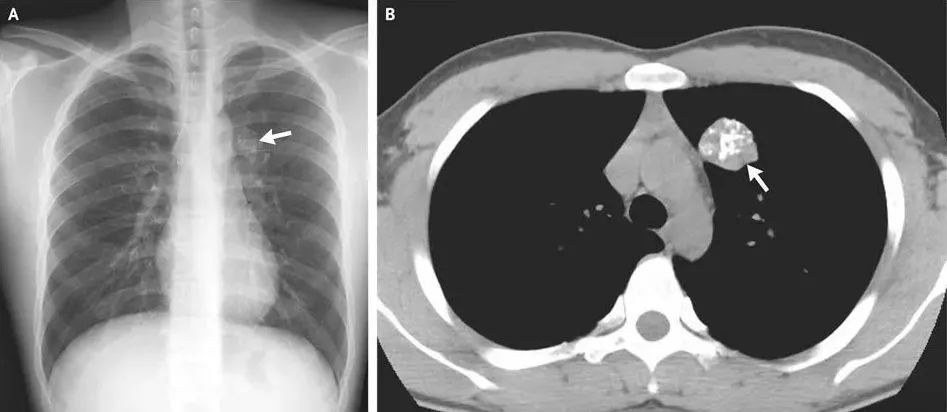

事实上,在X线片、 CT、钼靶、超声报告中,常常会出现“钙化”“钙化灶”的字样。据生命时报,钙化,指人体内的钙离子以磷酸盐或碳酸盐形式,发生沉积的过程。很多钙化是在人体病变修复过程中形成的,整个过程和伤口愈合结疤类似。通常表现为钙盐沉积在受损组织中,使这些组织变得坚硬。

人体绝大部分组织和器官内都可能出现钙化,比如头颅的脑膜、基底节区,胸部的肺、肋软骨、胸骨剑突,腹部的肝脏、肾脏,以及甲状腺、乳腺和前列腺等腺体,还有遍布身体的大多数动脉和静脉血管。钙化存在的广泛性也使得它成为体检和平时检查中影像学报告上的“常客”。

航空总医院影像科副主任申太忠介绍:“钙化不是疾病,而是一种体征。”钙化是否影响健康要根据其出现的部位、影像学特点、患者临床表现来确定。

通过检测钙化的发生位置和程度,医生可及时发现和诊断疾病,了解病情进展,评估治疗效果。钙化的发生与多种因素相关。